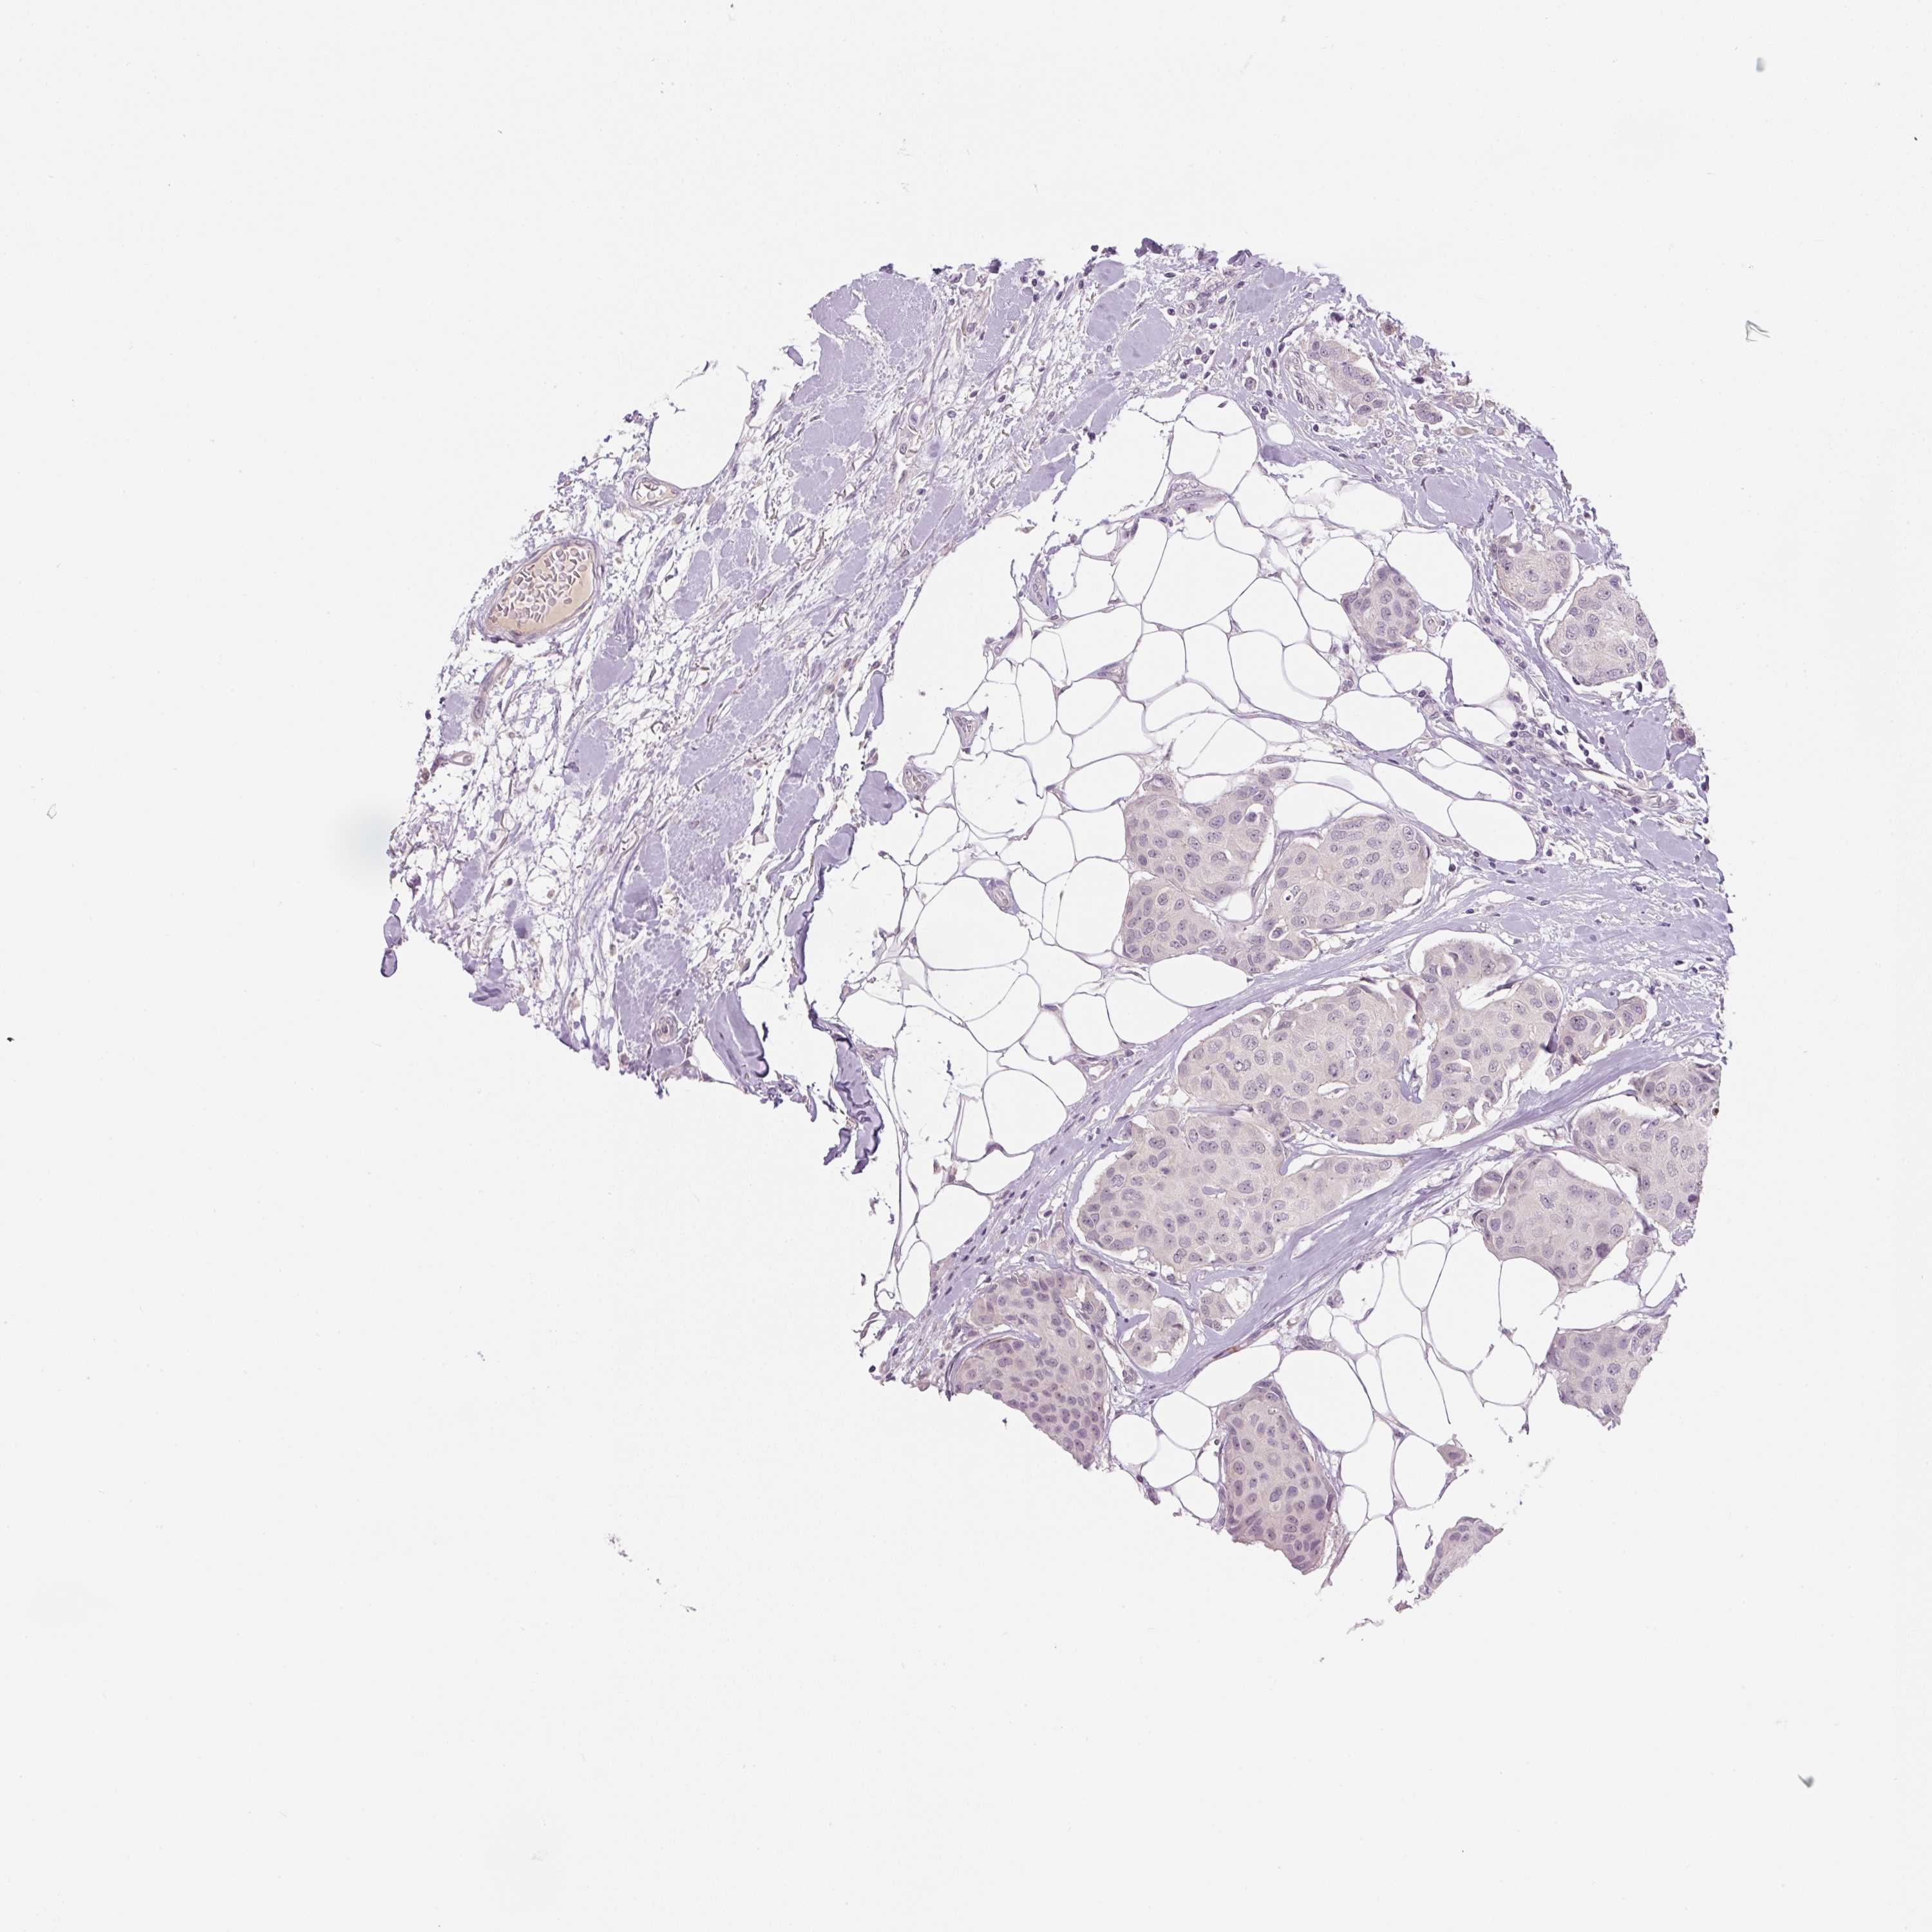

CANCER BREAST CANCER Show tissue menu

BRCA TCGA BRCA VALIDATION PROTEIN EXPRESSION